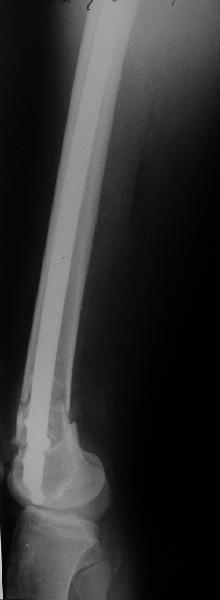

А в чем проблемы? Пример в приложении.

Насчет снимка Вами представленного - смотрится оч красиво, еще бы на функцию узнать...

I> Насчет снимка Вами представленного - смотрится оч красиво, еще бы на

I> функцию узнать...

В приложении функциональные снимки в 3 мес. и в 1 год.